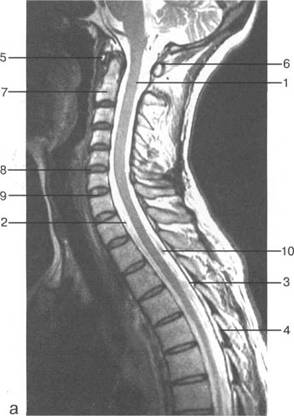

К моменту рождения (рис. 3.1) тело позвонка почти полностью состоит из к 141s183b 86;стной ткани, за исключением лимбусов, которые остаются хрящевыми. Дуга представлена двумя половинами, не слившимися ни с телом позвонка, ни между собой. Суставные отростки сохраняют перифе

fossa rhomboidea; pedunculus cerebellaris sup.; pedunculus cerebellaris medius; n. trigeminus; n. facialis; n. vestibulocochlearis; margo sup. partis petrosae; pedunculus cerebellaris inf.; tuberculi nuclei cuneati; tuberculi nuclei gracilis; sinus sigmoideus; n. glossopharingeus; n. vagus; n. accessories; n. hupoglossus; processus mastoideus; N.C. I; intumescentia cervicalis; radix dors.; ramus ventr. n. spinalis IV; ramus dors. n. spinalis IV; fasciculus gracilis; fasciculus cuneatus; ganglion spinale (Th. I).

MPT. Cw_v.